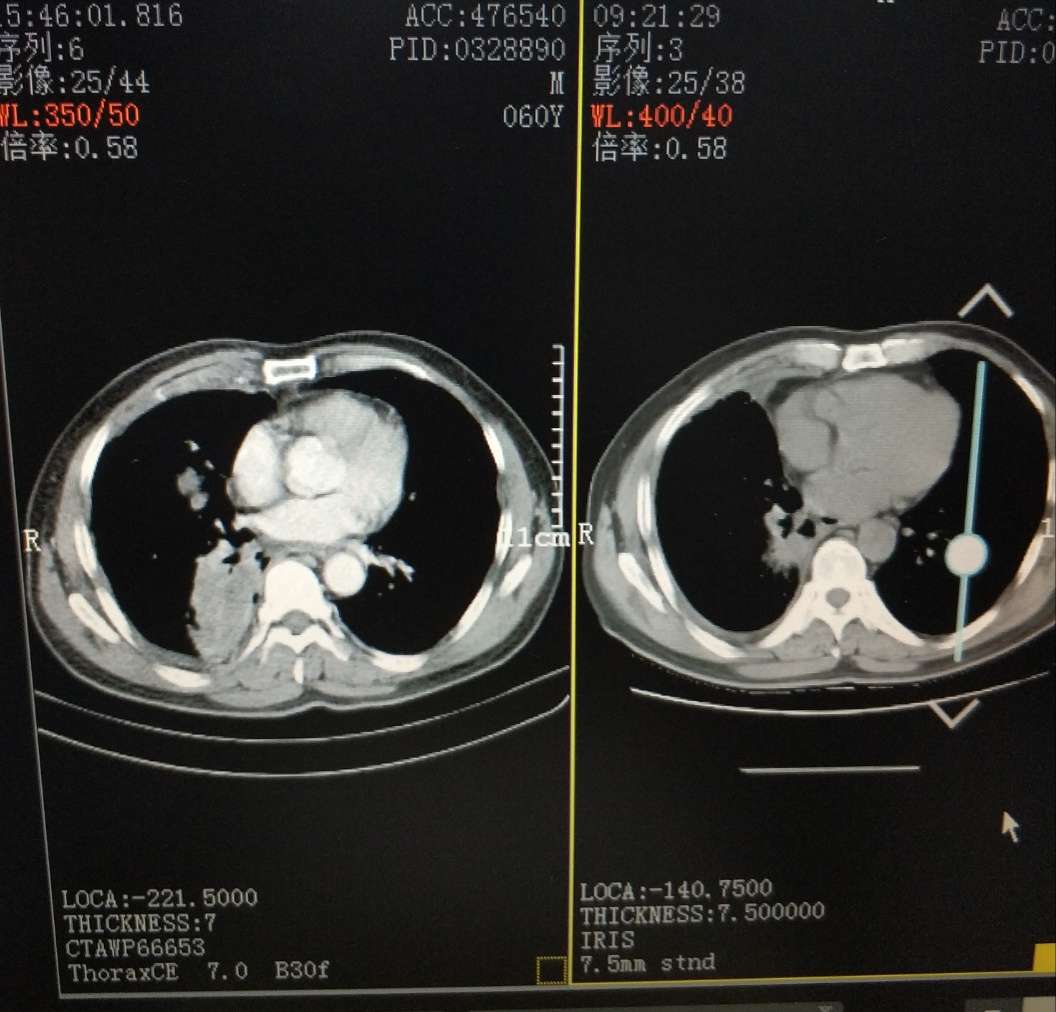

ct为前后吃易瑞沙一个月对比

易瑞沙前后一个月对比

一个月对比,现在的问题是胸水反反复复易瑞沙控制不了胸水,医生说效果不怎么好